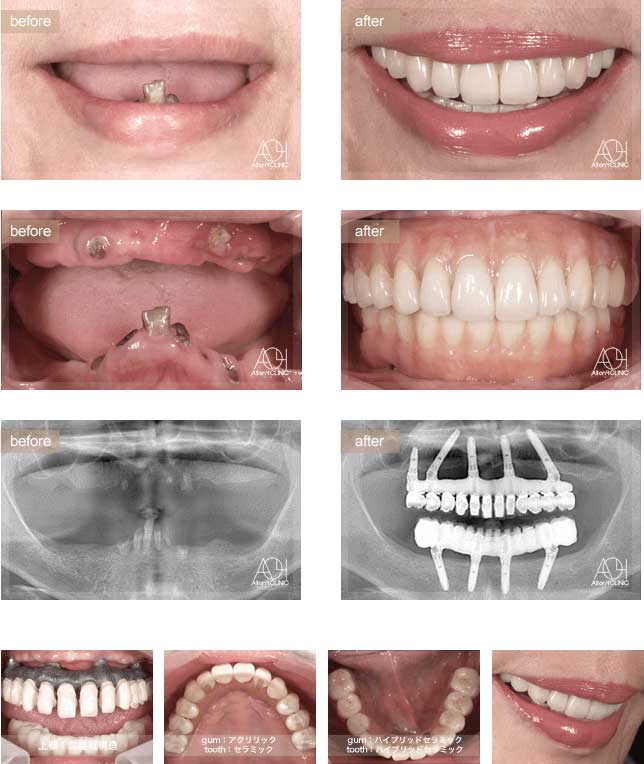

Treatment : All-on-4 zygoma

- Upper All-on-4

- Lower All-on-4

Age : 56 Sex : 男 S.T

| 主訴 | 仕事が忙しく歯には全く関心が無く、とうとう食事が困難になり治療を受ける事を決意。 |

| 治療内容 | ガイデッドサージェリーにてインプラント埋入。極めて骨量が少ないためザイゴマインプラントにて治療 |

| 治療費(総額) | ¥7,200,000(税抜)『モニター割引適用』 |

| リスク | 治療後の口腔管理が不適切な場合、埋入したインプラント周囲に感染・炎症を起こし、脱落する可能性がございます。 |